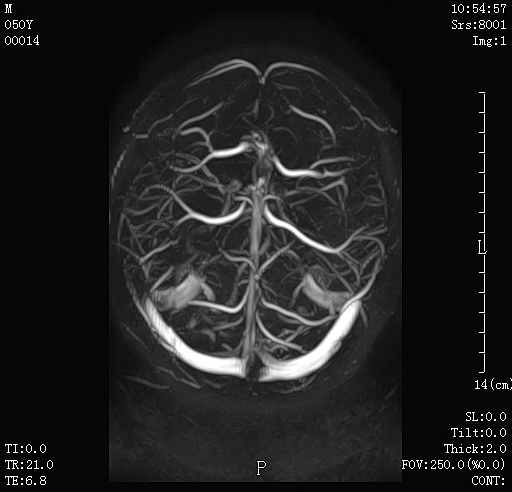

08 头颅磁共振静脉血管成像(MRV) 可用于疑有静脉窦血栓患者